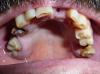

Nikk3 Опубликовано 14 мая, 2010 Поделиться Опубликовано 14 мая, 2010 Уважаемые стамотологи.Посоветуйте пож..что можно сделать в этой ситуации.На верхней челюсти 7, зуб подвижен и со сколом.Так сказали в клинике.Надо удалять.4 удалять.8 под вопросом..но там кариес и скол.1и6 тоже удалять.С номерами зубов ..может что и напутал.После предлагают поставить нейлоновый протез.Импланты ....говорят не мой случай т.к не кости.Но совсем не исключили(имплантацию). Ссылка на комментарий

Nikk3 Опубликовано 16 мая, 2010 Автор Поделиться Опубликовано 16 мая, 2010 Самое простое мостом 13-25 и замковый бюгель + поработать с нижним зубным рядом.Это относительно быстрое и бюджетное решение.Тем не менее эстетика будет вполне удовлетворительная. Можно решить вопрос имплантами-дольше, много дороже, много замороченнее, но тоже решаемо. Мостом 13-25 и замковый бюгель + поработать с нижним зубным рядом.Какие зубы при этом надо удалять.А какие оставлять?И что с низом..делать?Спасибо. Ссылка на комментарий

Nikk3 Опубликовано 16 мая, 2010 Автор Поделиться Опубликовано 16 мая, 2010 удалять все, что не входит в линию между 13-м и 25-м, это же очевидно.А с низом..оптимизировать окклюзию выборочно ставя одиночные коронки.Это значит,депульпировать и обтачивать линию между 13-м и 25-м.Мне не оч. хотелось-бы это делать.Может есть еще варианты?Спасибо за ответы. Ссылка на комментарий